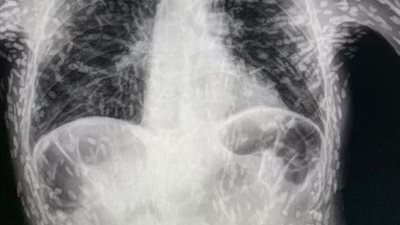

أشعة سينية تكشف حالة صادمة لمريض مصاب بالديدان الشريطية

الجمعة 05/05/2023 08:43 م